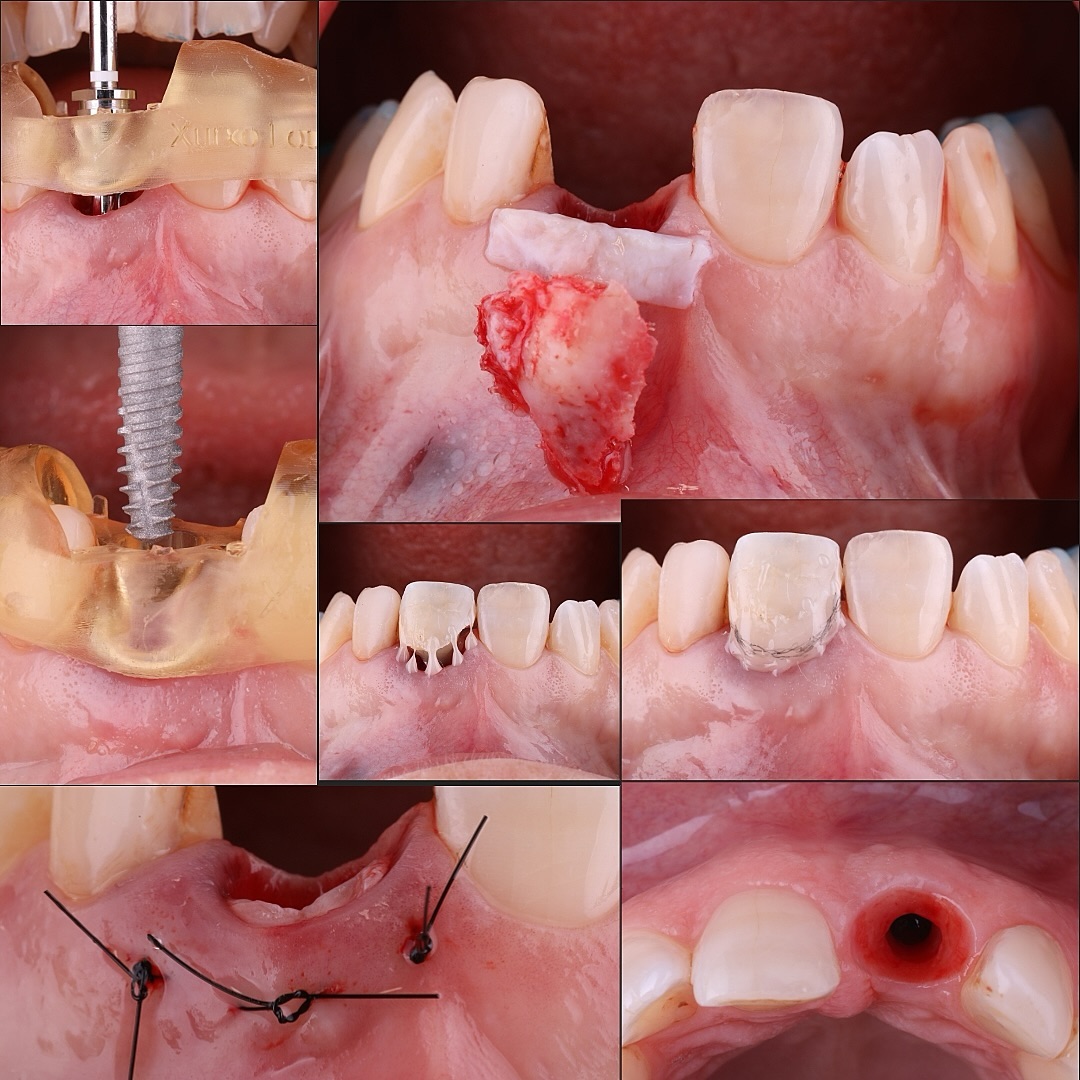

Pablo Pérez Lanza

Periodoncia y Cirugía Mucogingival Teruel, España

Paciente que presenta fractura del 1.1., a consecuencia de una reabsorción radicular previa. Se realiza la extracción de la pieza, con legrado minucioso del lecho. Se coloca un implante de superficie híbrida, en posición protésicamente guiada. Se obtiene un injerto de tejido conectivo, suturado en sobre vestibular. Se rellena el gap con aloinjertocorticoesponjoso, mezclado con L-PRF. Siguiendo la filosofía "One Abutment, One Time", se coloca un pilar de 10º no rotatorio de 3 mm de emergencia estrecha. Se adapta la corona provisional sobre un pilar tallable, para favorecer una cicatrización guiada por el futuro perfil de emergencia. Se restaura con una corona cementoatornillada de circonio sobre interfase no rotatoria.